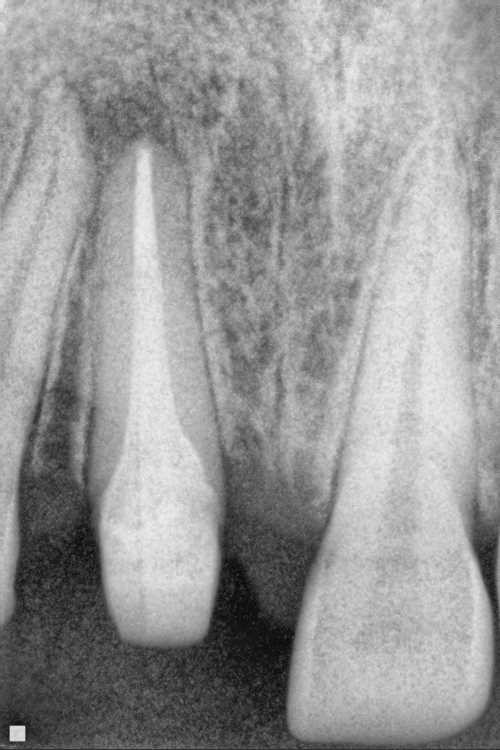

1.  What option can describe the post placement in the X ray bellow for the tooth # 2.5?